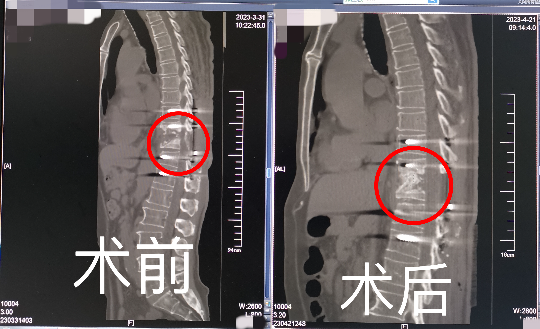

刘阿伯的第三次手术难度高、风险大。脊柱外科团队经过精密的术前设计准备,选择了经胸前路手术彻底清除了胸椎结核病灶,解除了脊髓神经的压迫。同时行胸椎病灶的植骨融合,重建了脊柱的稳定性。手术仅耗时1个半小时,手术出血很少。术后次日,刘阿伯即感到下肢麻木感消失。术后第4天,刘阿伯就开始下地行走,腿已经完全不麻木,也明显有力了。术后2周,刘阿伯已经能像常人一样正常行走,排大便也已恢复为正常的一天一次。